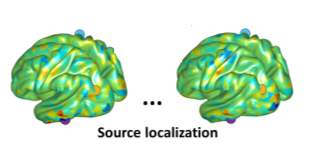

Our researchers are using Kelvin2 to tackle a range of complex simulations, data analysis, and modelling in fields such as Neurotechnology, Precision medicine and Metabolomics.

From neutron star collision to ground breaking cancer research to eco-designing for the future take a look at some of the groundbreaking studies carried out by NI-HPC users!